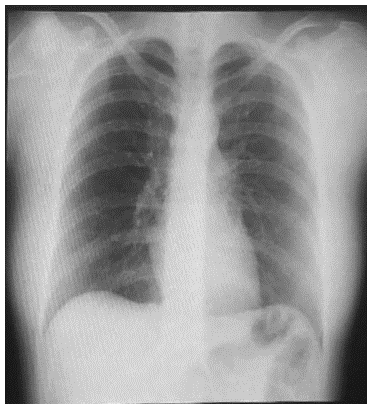

A 29 year-old female without significant clinical histories besides an appendectomy, presents with a clinical picture of 8 hours of moderate generalized abdominal pain following a programmed colonoscopic 12mm sigmoidal polyp resection. At presentation the patient denied vomiting or fever, physical examination showed generalized abdominal pain without rebound tenderness or signs of peritoneal irritation along with mild distention. Vital signs showed a 115/70 mmHg blood pressure, 75 bpm heart rate, 37.1 degrees Celsius, temperature and 92% oxygen saturation. Blood work showed normal renal function, coagulation and electrolytes, with significant leukocytosis of 24.830, neutrophils 90,9% along with a C-Reac-tive Protein of 124 mg/L and normal hemoglobin levels. Arterial blood gases showed no acid-base abnormalities or elevated levels of lactate. The patient was first seen by the emergency medical team, which ordered chest and abdominal x-rays that exhibited no signs of intestinal obstruction or pneumoperitoneum. (Figure 1 and 2).